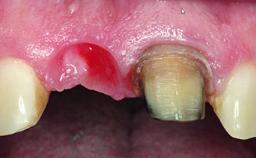

A 32-year-old female Caucasian patient with a compromised maxillary right central incisor was referred to us by a general dentist. Her chief complaints were discomfort and mobility of tooth 11 with unsatisfactory esthetics due to discoloration. The patient reported a previous trauma, some years earlier, as the origin of pathology on the afflicted tooth. Anamnesis was negative for any other dental or periodontal pathology in the remaining dentition. The patient did not take any medication and reported to be a light smoker (5–10 cigs/day). She had high esthetic expectations of her treatment. The extraoral examination revealed a high smile line with full exposure of her maxillary teeth and surrounding soft tissue in the area between the second premolars.

Soft Tissue Contour and Volume Slightly compromised